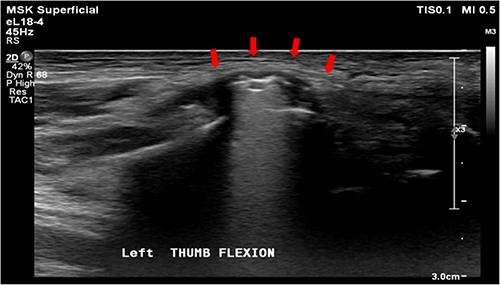

A 61-year-old male who denied any systemic disease, with a past medical history of a left distal radial fracture, which was treated with ORIF with a plate on 29 January 2017. He presented to the plastic surgery Outpatient Department (OPD) in July 2020 with a protruding mass over his left palmar wrist, which had been causing him pain for the past 3 weeks. On examination, poor flexion of the left thumb was noted. Upon suspicion of a ruptured FPL tendon, a sonogram was arranged, which confirmed the diagnosis (Fig. 1). After discussion with the patient, it was decided that he would undergo surgery.

Sonogram of the left wrist showing a ruptured FPL tendon. The arrow points to the discontinuity in the tendon, indicating the site of rupture.